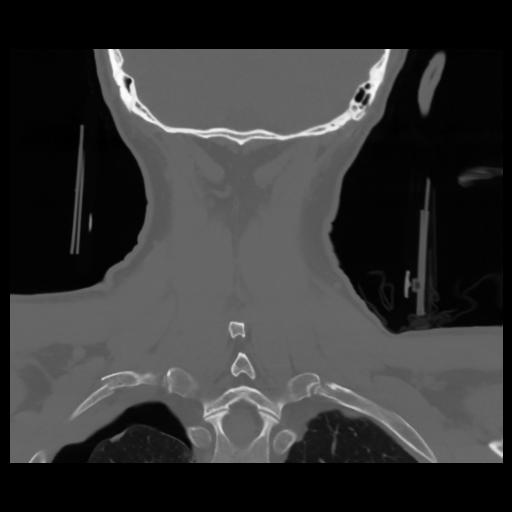

13 P.BLANDAS,,Coronal,2.000,P.BLANDAS,Coronal,